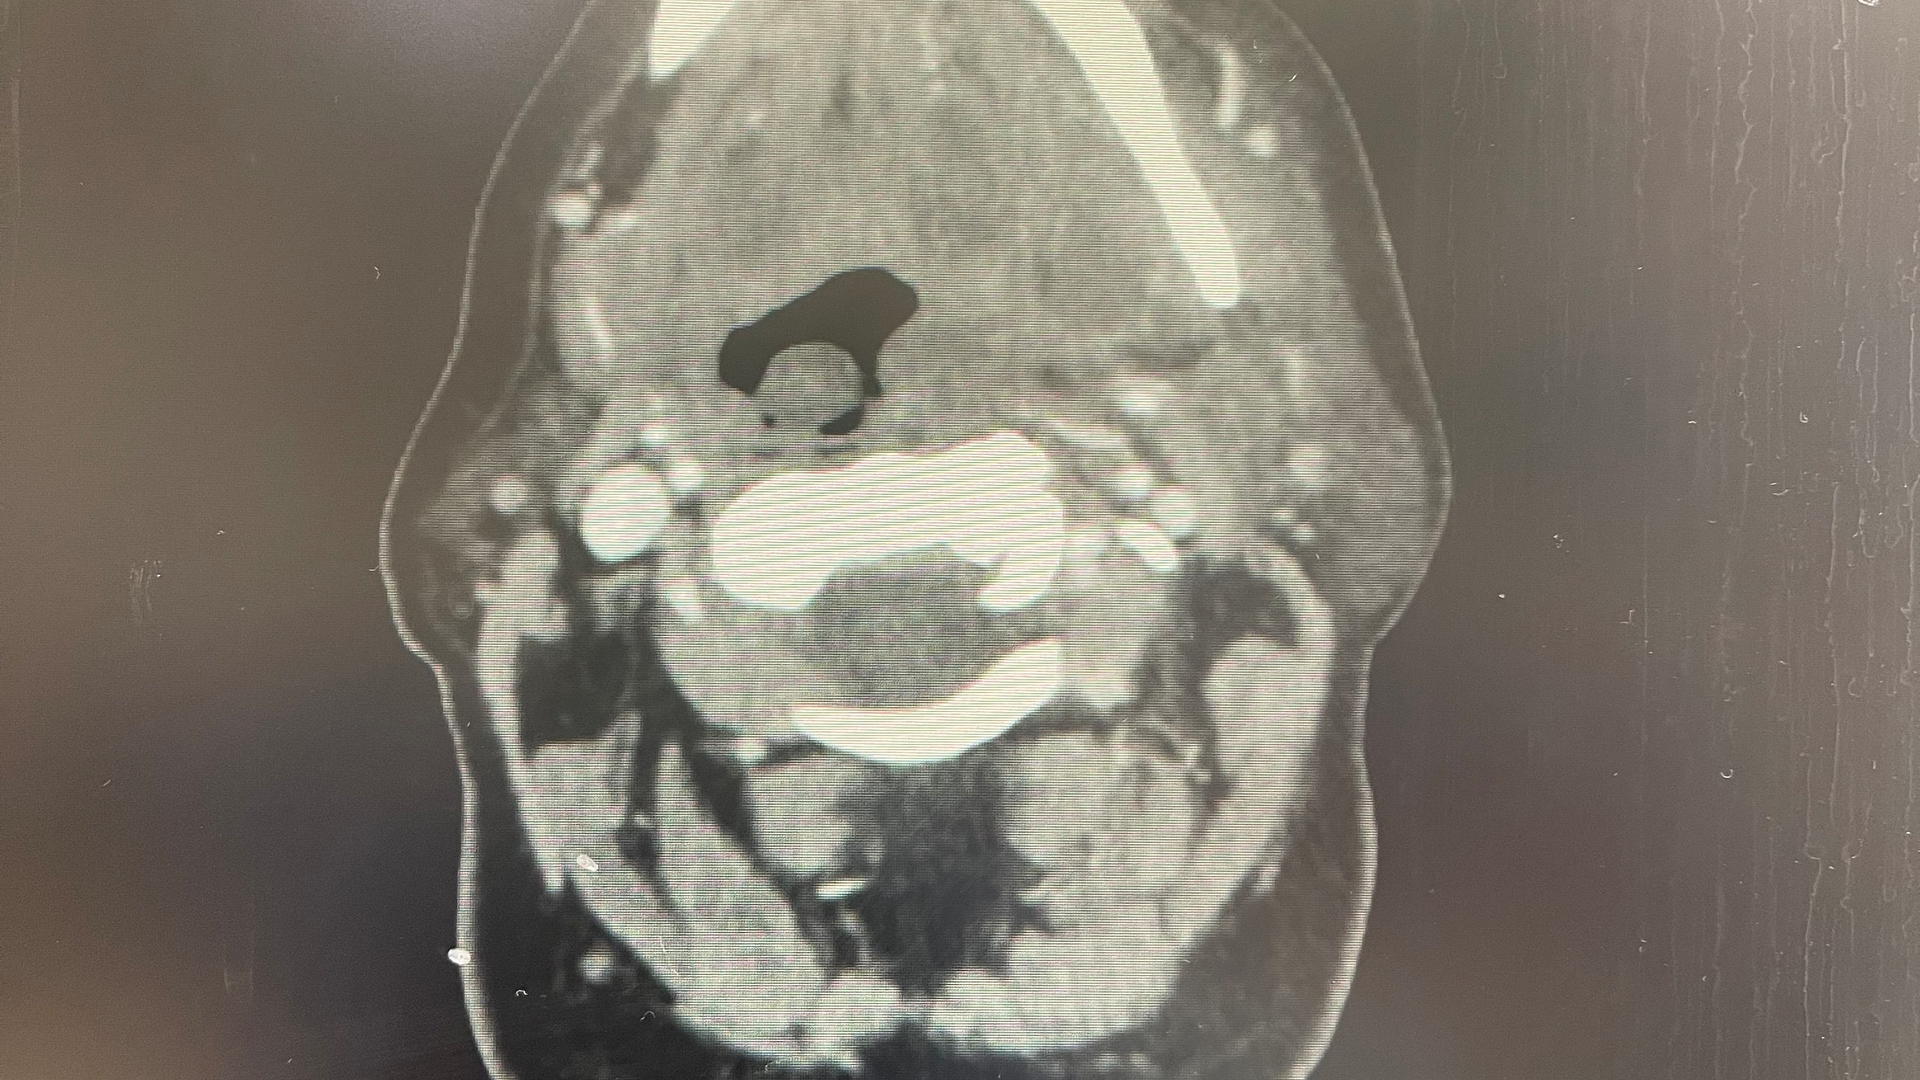

Signs of a facial infection include facial asymmetry in the form of swelling on one side of the face. The face will feel firm, warm, and tender to the touch, and redness of the skin will develop in time. It often starts with dental pain or tooth pain inside the mouth. It can also be pain inside the mouth around the tooth. As it progresses, you may see some intraoral drainage coming from the associated tooth. Infections originating from the skin will often present with external drainage. Severe odontogenic (caused by a bad tooth) infections may even spread and become so large they break through the skin.

There are some spaces around the face, called potential spaces, where the fluid can collect. Some of the spaces inside the jaw and adjacent to the throat can get very dangerous. That’s why it’s important to treat facial abscesses as soon as possible, usually within 24 hours.

Significant facial infections that require surgery are taken care of in a hospital setting. The patient is admitted to the hospital, started on IV antibiotics and pain meds, and planned for surgical incision and drainage (commonly called I&D) often within 24 hours, based on the severity and immediate risk of spread. Patients can expect a one- to three-day hospital stay depending on their response, recovery, and need for monitoring. During the hospital stay, the patient remains on antibiotics and pain meds through an IV, both of which will be converted to oral medications upon discharge. Most surgeons also require at least one postoperative visit to check progress.